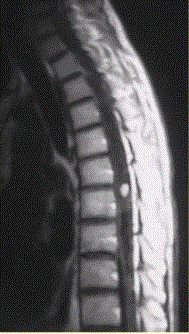

问题 患者女,45岁,胸部不适。影像学检查结果如下图所示。 关于成血管细胞瘤,正确的是

选项 A.脊髓内肿瘤 B.X线检查无阳性发现 C.明显增强的血管性壁结节对定性诊断价值 D.可多发,并伴发von-Hippel-lindau综合征 E.肿瘤上下或肿瘤内区域内见葡状生长的流空信号,可以确诊 F.发病率较低